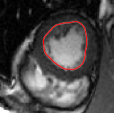

V-C LV and RV Segmentation: Quantitative Comparison to Commercial Software

We show experiments demonstrating the main use of our algorithm: in improving the prediction step of interactive segmentation methods. We show that less interaction is needed with our approach than a recent and widely used commercial cardiac segmentation software, Segment from Medviso [15, 44]. We perform quantitative assessment of the tracking performance of our method and compare it to Medviso. The evaluation was carried out on publicly available data sets, the MICCAI Left Ventricle Dataset [37] and the MICCAI Right Ventricle Dataset [25]. The validation dataset from [37] consists of 15 sets of cardiac cine-MRI images. Each set contains 6 to 20 2D slices from a 3D image, with each slice having 20 images of the cardiac phases. Similarly, the data set [25] contains 16 sets of cardiac cine-MRI images, each containing about 10 slices of 20 phases each. These data sets contain ground truth segmentations for left and right ventricles respectively (unfortunately ground truth for both the LV and RV is not available on a single dataset that we are aware of). Both methods start with the same initially correct segmentation, and subsequent frames are segmented via propagation. No manual interaction is used as we wish to show that our method would require less interaction. The regularity parameter in our method is found by choosing so that the results are closest to ground truth in a few training cases. The same parameter is then used for all other cases.

Figures 8 and 9 shows some sample tracking results of the proposed method and Medviso on full cardiac cycles of two different cases on both the LV dataset and the RV dataset. The ground truth (yellow) is superimposed when available. A summary of the results on the entire datasets is shown in Table I. The accuracy with respect to ground truth is measured using average perpendicular distance (APD) and dice metric (DM) for left ventricle, and Hausdorff distance (HD) and DM for the right ventricle. These metrics are chosen since they are the standard ones used on these datasets. Both qualitative and quantitative results show that our proposed method leads to more accurate segmentation of the ventricles and thus leads to less interaction than segmentation propagation schemes in than Medviso.